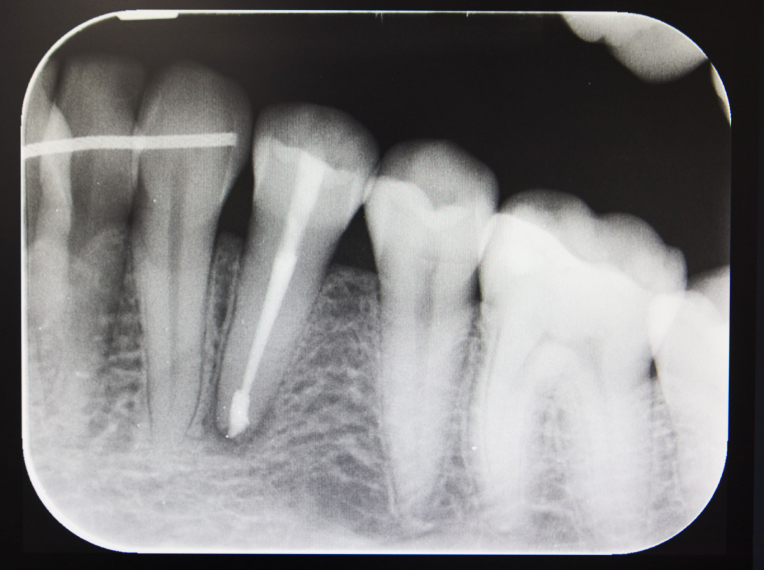

1. Firstly, your specialist will identify the problem at hand, and will subsequently take x-rays of the relevant tooth and the area around the tooth.

2. Following this x-ray process, when it comes to the procedure itself, the tooth area will be numbed with a local anaesthetic. In addition to this, your tooth will be covered with a rubber dam or sheet, which isolates the relevant tooth from the rest.

3. When it comes to the removal process, the dental practitioner will remove the diseased pulp inside and clean and seal the tooth root canal system. The pulp chamber is accessed from the top of the tooth, and once cleaned, the root canals are filled with a natural material called gutta-percha.